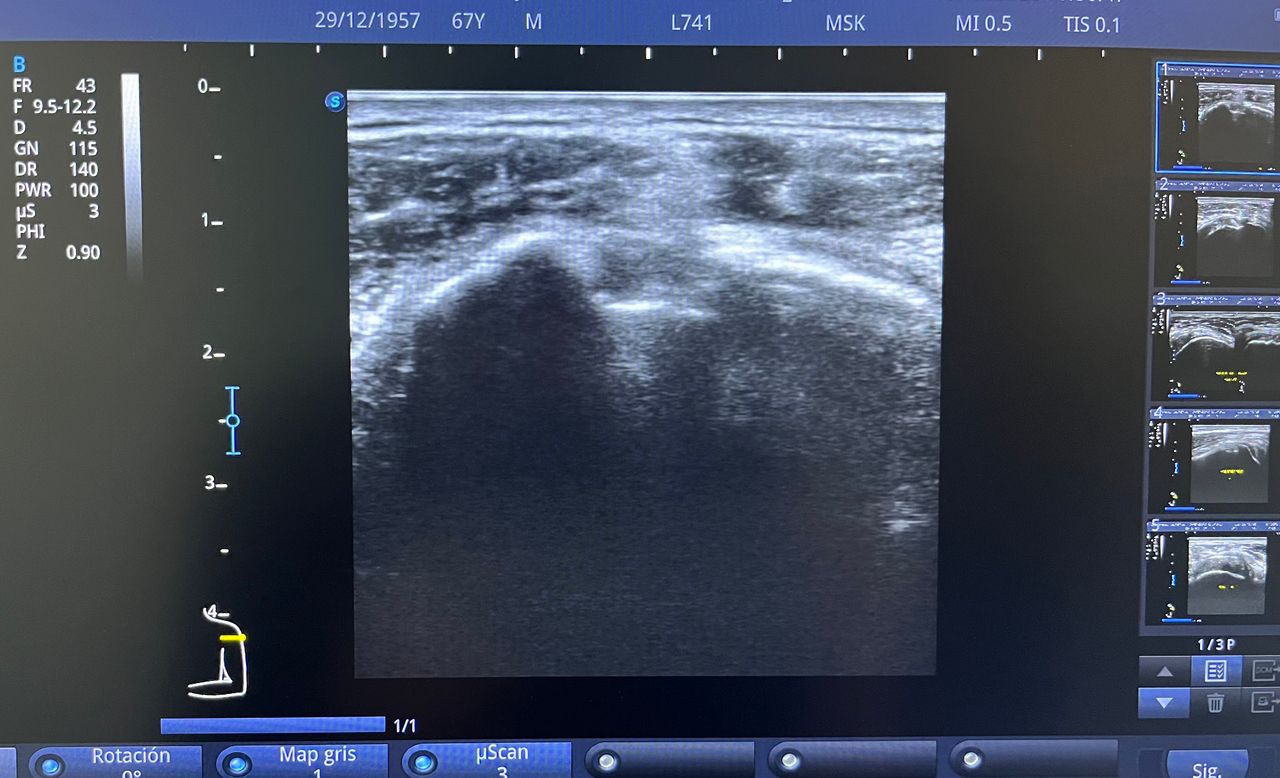

Médico general con 15 años de experiencia, master en enfermedades infecciosas y antibioticoterapia por parte de la Universidad Cardenal Herrera en Valencia, ademas de diversos diplomados en el área de Infectología y Parasitología, Urgencias, Imagenología y Medicina del Trabajo. He laborado en Hospitales y Clínicas en el área de Urgencias, en Laboratorios realizando estudios de Imagen, en especifico ultrasonidos de todo tipo desde básicos hasta avanzados incluidos los obstétricos estructurales, en Secretaría de Salud del Estado de Querétaro realizando ultrasonidos obstétricos para la detección de malformaciones en los tres trimestres del embarazo en diversos centros de salud, como médico de Empresas en el campo de Salud Laboral y actualmente en este consultorio en donde para su mejor atención y siempre buscando integrar la mayoría de las herramientas diagnosticas cuento con equipo de ultrasonido como apoyo en la exploración del paciente o como servicio diagnostico por imagen, realizo ultrasonidos convencionales (hepatobiliar (hígado, páncreas, vesícula y bazo), vías urinarias, ginecológico abdominal y transvaginal, tiroideo, prostático, testicular, pared abdominal) y especializados (dopler obstétrico en los 3 trimestres de embarazo), musculoesquelético en lesiones deportivas. También cuento con un equipo de electrocardiograma de 12 derivaciones para monitoreo completo del funcionamiento cardiaco, espirometria para evaluar la función pulmonar en la consulta, pruebas rápidas que se realizan en consultorio para detectar de forma mas precisa enfermedades infecciosas como Influenza A y B, covid19, infecciones urinarias, dengue, zika, chikungunya. Cuento con diversas vacunas para prevención de enfermedades. Siempre con el objetivo de dar el mejor servicio y atención a su salud. Lo espero en consulta para escucharlo y estudiar su caso de la forma más completa posible, estoy seguro de que tendremos las mejores opciones para su tratamiento. Mi tranquilidad es que usted se vaya con todas sus preguntas e inquietudes resueltas.